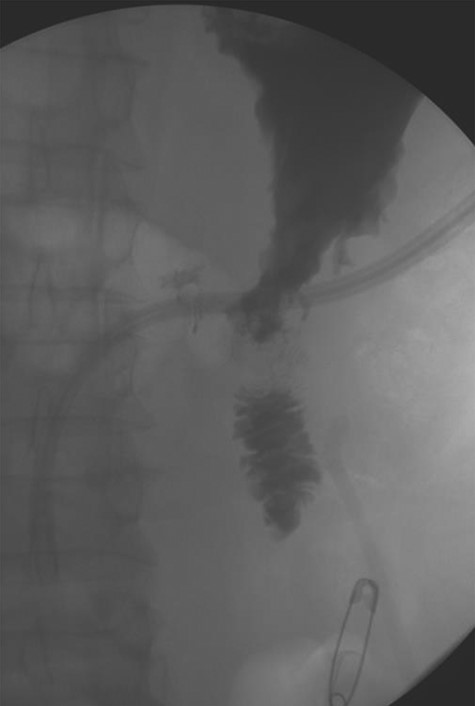

A laparoscopic distal gastrectomy and partial duodenectomy with antecolic antegastric Roux-en-Y reconstruction with a pancreaticobiliary limb of 50 cm and the Roux limb of 50 cm and esophagogastroduodenoscopy were performed. As the patient had been positive for Helicobacter pylori on endoscopic biopsy and there was increased concern for his use of alcohol as well as his living situation, a definitive acid suppression operation was also performed. The pathology returned as chronic gastritis with associated ulcer with mild metaplasia, the H. pylori on immunohistochemistry was positive. The patient on postoperative day (POD) 1 had a swallow study, which demonstrated a patent gastrojejunostomy with adequate flow distally (Fig. 5). On POD 5 the patient was discharged on a proton pump inhibitor and treatment for his H. pylori.